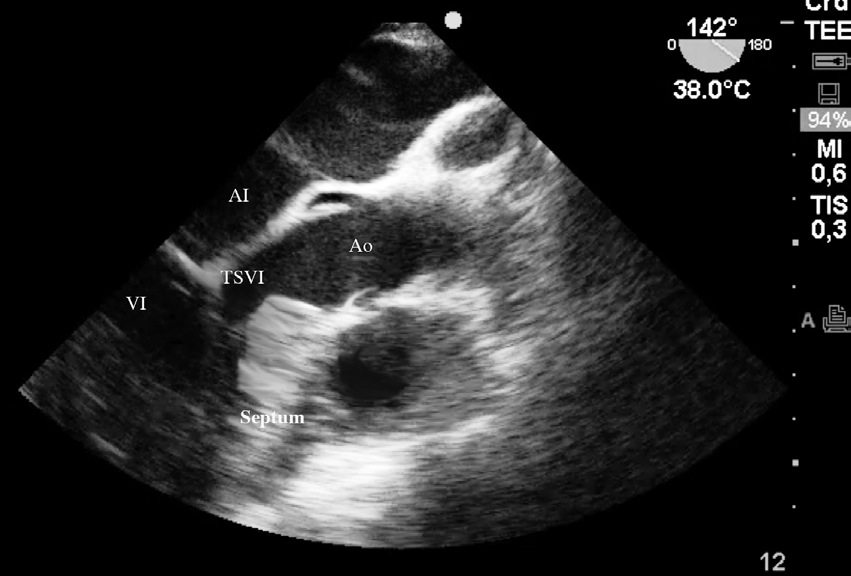

Al ingreso al pabellón quirúrgico se monitoriza con oximetría de pulso, presión arterial invasiva y electrocardiografía continua de tres derivaciones, que mostraban una frecuencia cardiaca normal. Se colocó un catéter epidural lumbar G18 en el espacio L2-L3 para proporcionar analgesia postoperatoria y se induce anestesia general endovenosa en modo TCI (target-controlled infusión) con propofol y remifentanil, para una concentración sitio efecto de 2,6 ug ml-1 y 4,5 ng ml-1, respectivamente, como relajante muscular se utilizó rocuronio 0,6 mg kg-1. Inmediatamente de realizada la intubación endotraqueal se instaló un transductor multiplanar (3-8 Mhz) de ecocardiografía transesofágica (FujiFilm Sonosite Edge®) para monitorización intraoperatoria, obteniéndose mediciones basales de fracción de eyección y de precarga, la primera en un plano medio esofágico, visión de cuatro cámaras con método de Simpson, constatándose una fracción de eyección de 55% y la segunda en una visión transgástrica profunda en un eje corto midiendo el área de fin de diástole del ventrículo izquierdo como indicador del volumen de fin de diástole , siendo este de 9 cm2 (valor normal: 8-14 cm2) Durante la cirugía se mantuvo una vigilancia continua del tracto de salida del ventrículo izquierdo (TSVI) a través de la visión de cuatro cámaras a 0º y 130º para la detección precoz de SAM (Figura 1). El desarrollo de la cirugía transcurrió sin incidentes hasta el momento del alumbramiento. Luego de la administración de oxitocina endovenosa (syntocinon®) 2 UI, presentó hipotensión sistólica de 65 mm Hg con una frecuencia cardiaca de 125 latidos por minuto. Las imágenes ecocardiográficas en el eje corto intragástrico mostraban una disminución del área de fin de diástole del ventrículo izquierdo de menos de 8 cm2 y en el plano medio esofágico visión de cuatro cámaras una disminución cualitativa del diámetro del TSVI en base al desplazamiento del velo anterior de la válvula mitral sin obstrucción total (Figura 2). El doppler color de la válvula mitral mostraba un jet sistólico de regurgitación que abarcaba dos tercios de la aurícula izquierda. En base a estas imágenes se determinó administrar bolos de cristaloides de 100 ml para mantener un área de fin de diástole ventricular mayor de 10 cm2. Como la frecuencia cardiaca permaneció elevada se inició bloqueo beta mimético con propanolol, en bolos de 0,5 mg hasta un total de 1,5 mg endovenoso, obteniéndose con estas medidas estabilidad hemodinámica. En las imágenes ecocardiográficas se observó nuevamente un normal desplazamiento del velo anterior de la válvula mitral.

Figura 1 Imagen ecocardiográfica en esófago medio a 142º que muestra la hipertrofia septal y tracto salida ventrículo izquierdo (TSVI). Aurícula Izquierda (AI). Ventrículo Izquierdo (VI). Aorta (Ao).